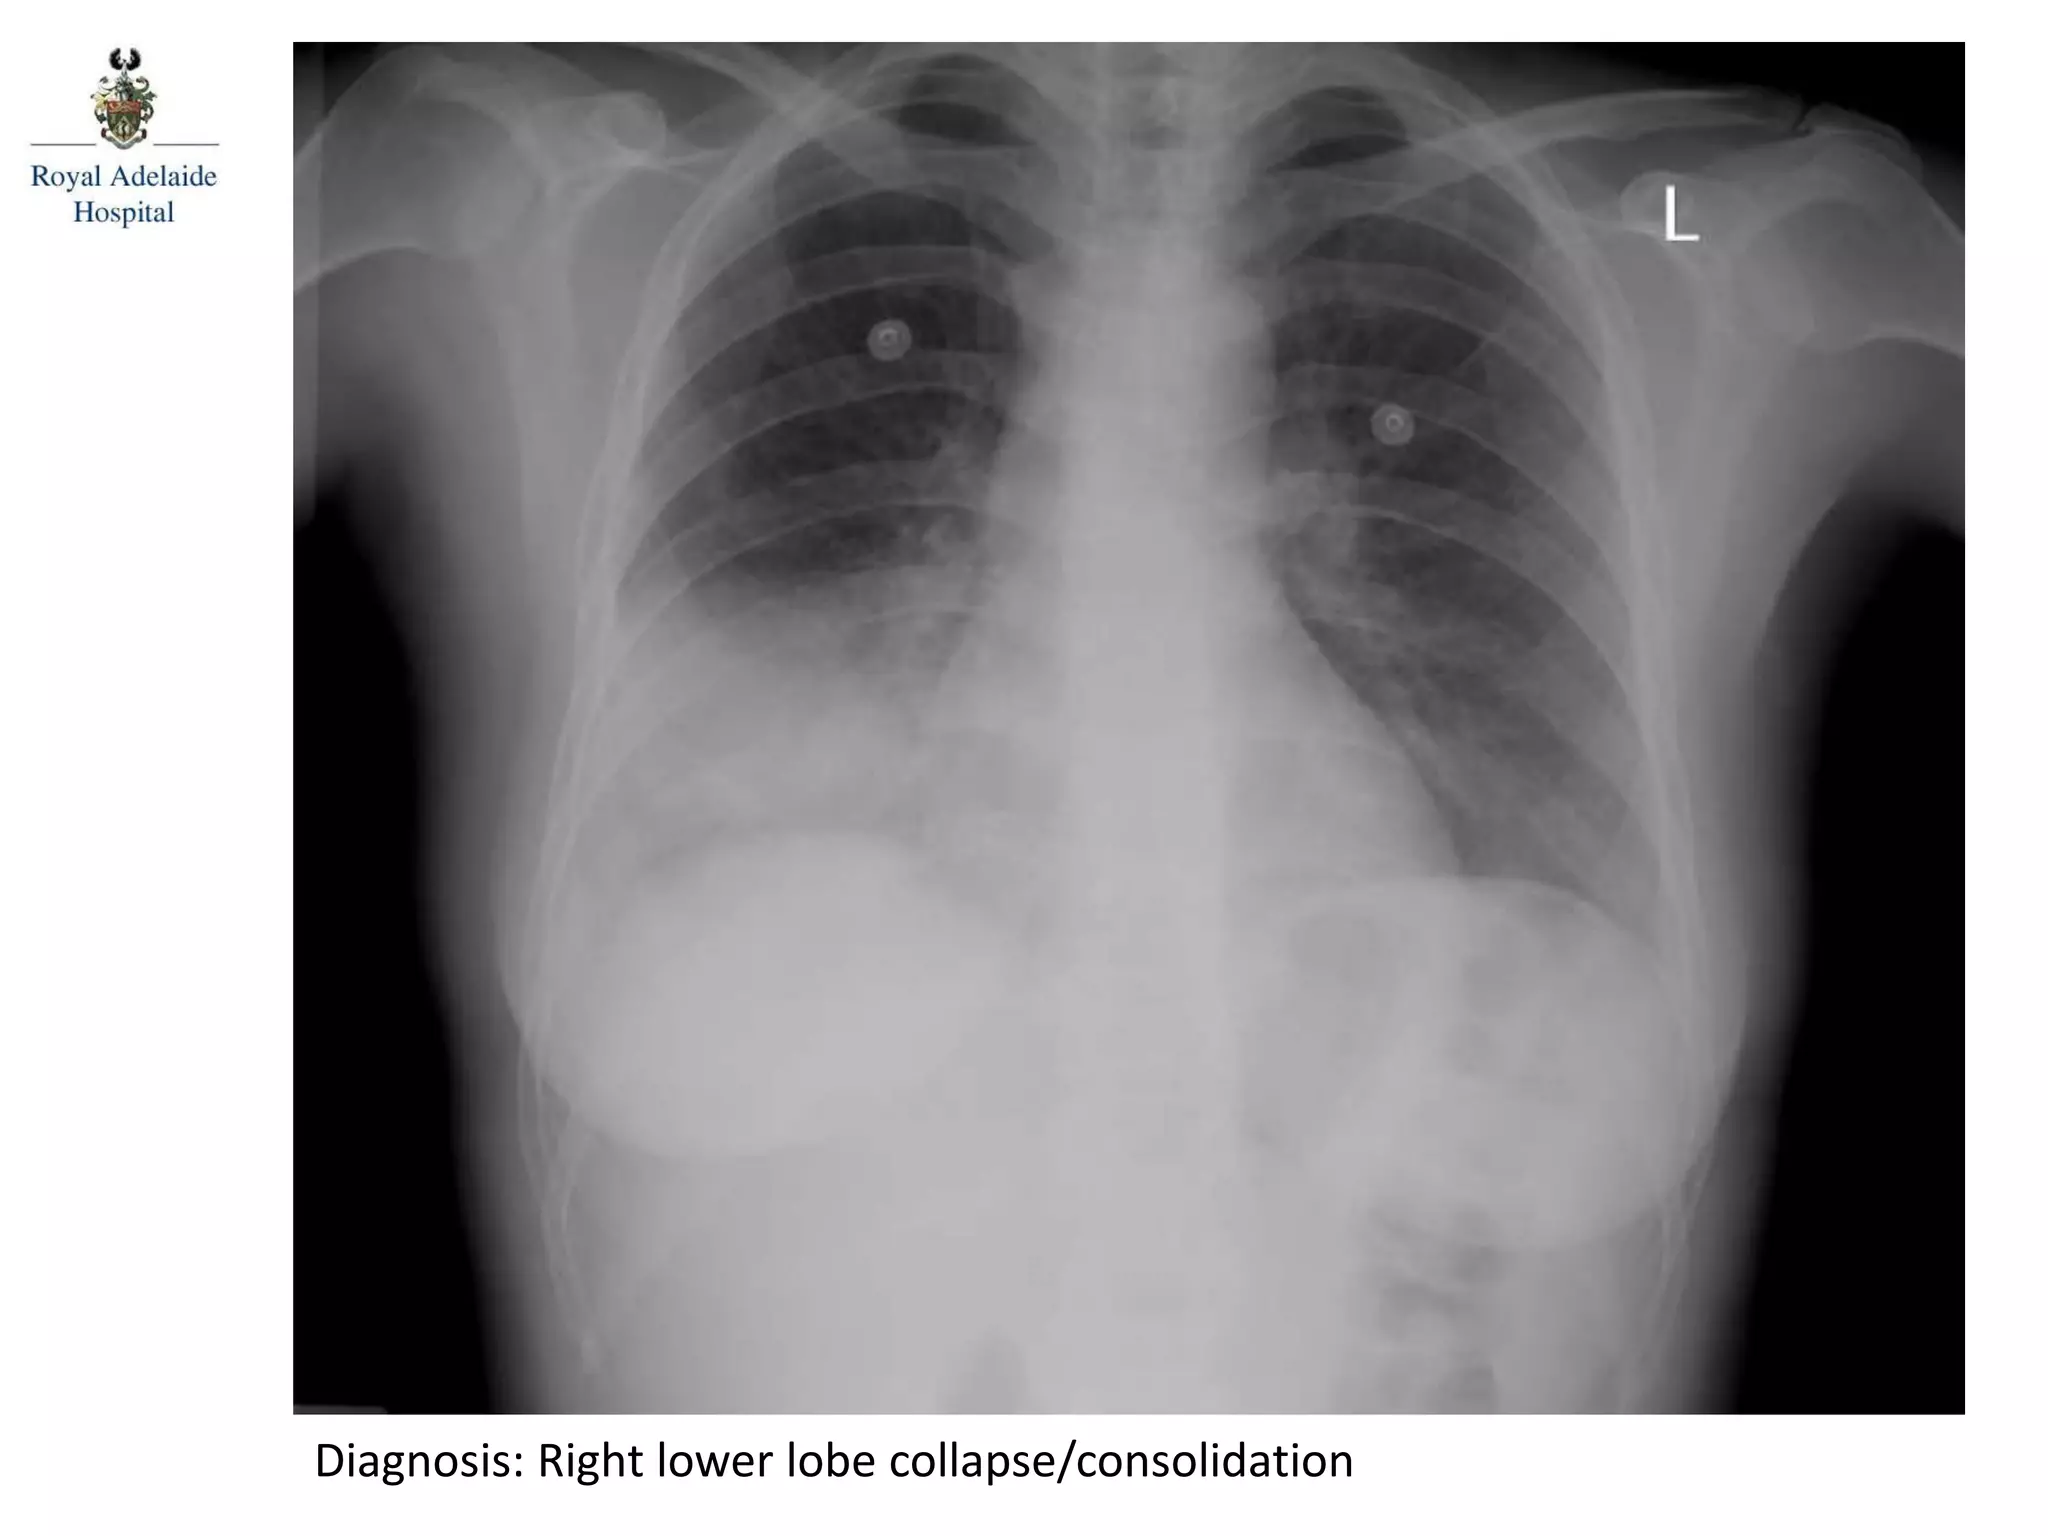

Diagnosis: Right lower lobe collapse/consolidation